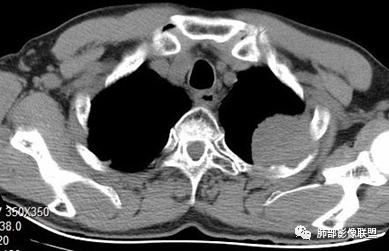

看看这个,骨头都侵袭了。

今天的病例有些伪影。

看起来就觉得放射状伪影。

我就不知道这些是胸水,伪影导致密度增高?还是胸膜增厚?

而且旁边这么宽的少,所以觉得很奇怪,不太符合,我是怀疑与照片有关。

你对比一下两侧的密度。肌肉密度不一样。